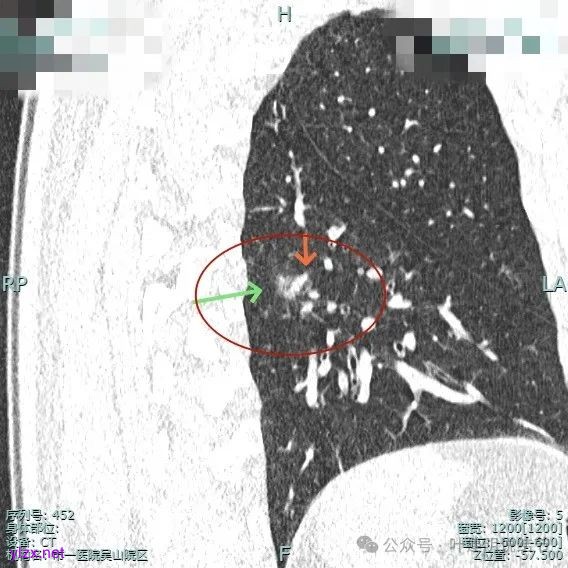

靶重建后见主病灶密度不均,灶内混合密度,整体轮廓较为清楚,表面不平,整体有一定膨胀感。

主病灶实性成分明显,表面有毛刺,边缘不平毛糙;次病灶密度纯且淡,轮廓清楚。

主病灶有血管进展与异常增粗,灶内有实性成分,中间有小空泡征。

主病灶血管进入,灶内空泡,表面浅分叶,整体轮廓较清。